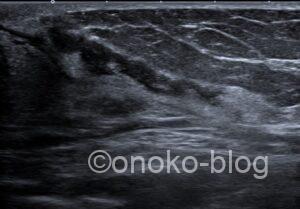

血流シグナルも、エラストグラフィーも悪性を疑う所見は確認できませんでしたが

悪くてDCISとかかな~なんて考えつつ、レポートを作成して提出。

精査目的で他施設さんに紹介し、結果は細菌感染でした。

悪性ではなくて良かったと思う気持ちと、

細菌感染だとエコーはこうやって見えるんだなぁと学びました。

異常分泌物がある場合の乳腺エコーは、

やはり乳頭部付近を念入りにスキャンすることが大切かなあと思っています。

加えてカラードプラで血流をチェックします。

今回の症例もですが、やはり乳頭部付近はエラストグラフィの評価が難しいんですよね…